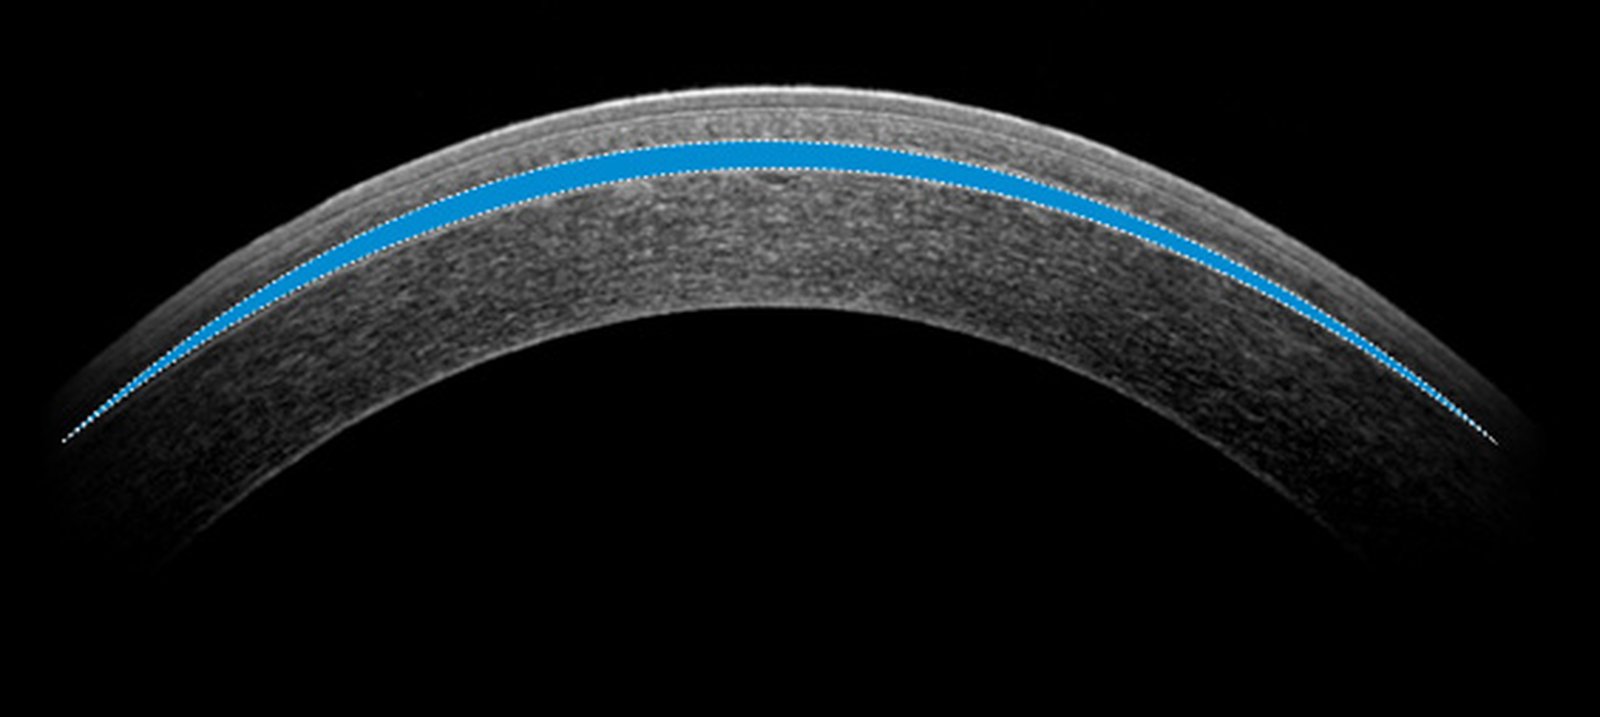

스마일라식은 각막 절개 범위를 최소화한 시력교정술로, 비교적 빠른 회복과 안정성을 장점으로 꼽혀요. 수술 다음 날부터 일상생활이 가능한 경우도 많아 부담이 적은 수술로 인식되기도 해요.

수술 후 초기에는 각막 절개 부위와 각막 실질층이 안정화되는 시기예요. 이때 눈을 세게 비비거나 압박을 가하면 각막에 물리적 자극이 전달될 수 있어요. 수술 후 시간이 지나 각막이 회복되어도 눈 건강을 위해서는 의식적으로라도 눈을 만지지 않는 습관을 가지는 것이 좋아요.